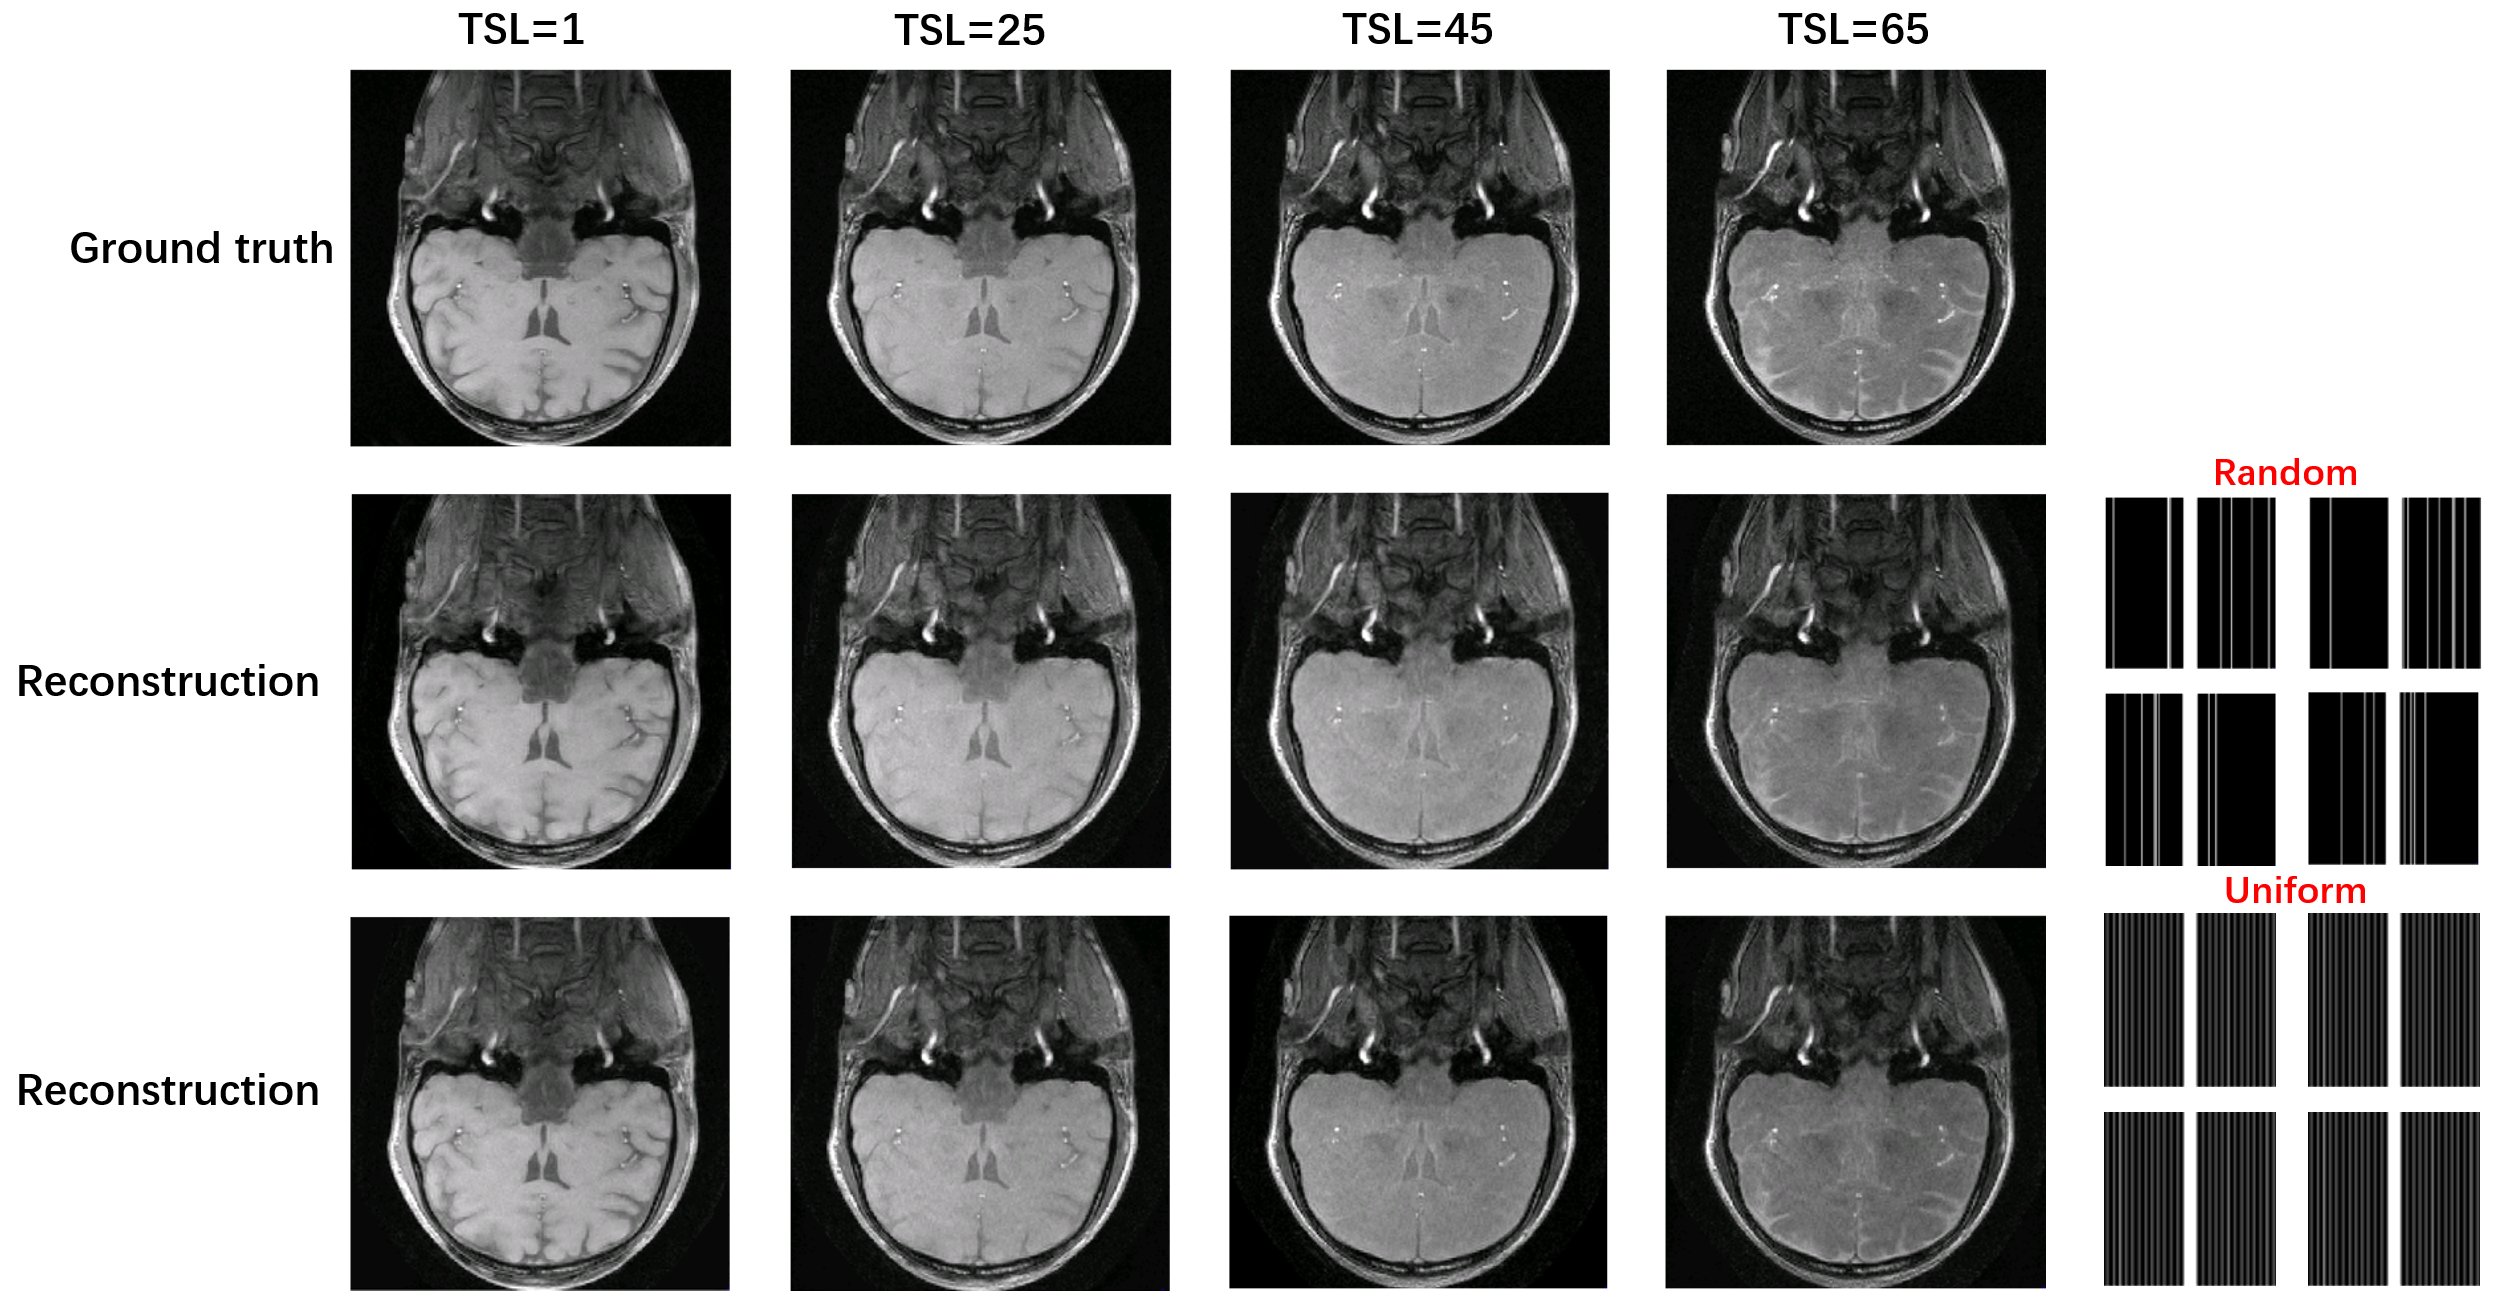

A schematic diagram of the bidirectional process is given in Fig. 1. The weighted images corresponding to different TSL are perturbed with Gaussian noise of differentintensities. The results in Fig.2 show that the uniform pattern has a certaintranscendence relative to the random pattern in terms of artifact-free. From T1rho maps by exploiting curve fitting, the proposed method is capable of quantification of T1rho relaxation times in uniform pattern with 8-fold acceleration.

Fig. 3 The T1rho map of the proposed method under different acceleration patterns using curve fitting to assess the feasibility of the proposed method. One can see that the T1rho map can be obtained under both sampling templates closer to the ground truth. The proposed method under uniformly sampled templates is superior for T1rho quantification relative to random templates. The red arrows point out the superiority of the detail section in the uniform pattern.